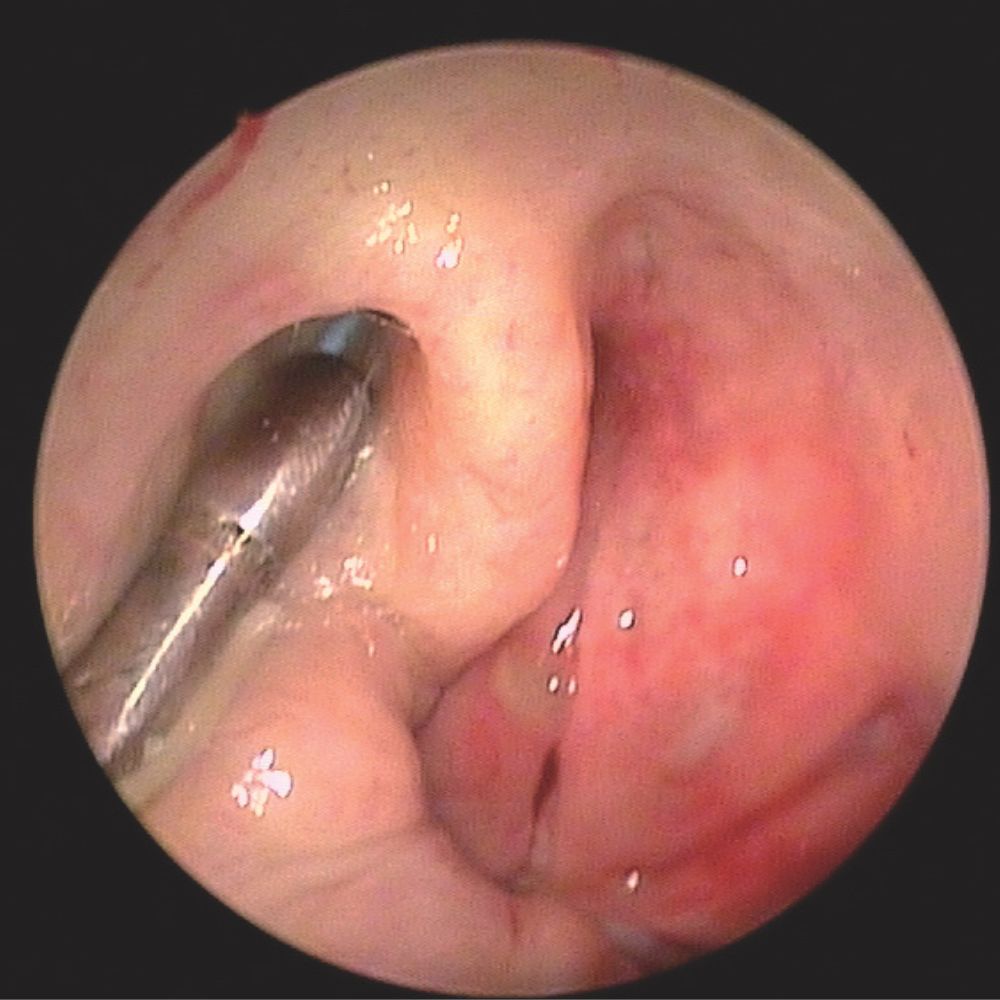

System TubaVent to nowatorska, małoinwazyjna i bezpieczna metoda leczenia chronicznych dysfunkcji trąbki Eustachiusza. Kateter balonowy pod kontrolą endoskopu wprowadzany jest do trąbki słuchowej za pomocą specjalnie zaprojektowanego insertera i mikro-endoskopu. Przy użyciu dedykowanej, pompy do części dystalnej kateteru wprowadza się płyn pod ściśle określonym ciśnieniem. Efektem tego zabiegu jest powiększenie światła trąbki słuchowej i przywrócenie jej prawidłowego funkcjonowania. Zabieg wykonywany jest w znieczuleniu miejscowym lub ogólnym.

Liczne badania naukowe potwierdzają bardzo wysoką skuteczność i efektywność tej metody. System TubaVent z powodzeniem zastosowano już u ponad 50 000 pacjentów na całym świecie.